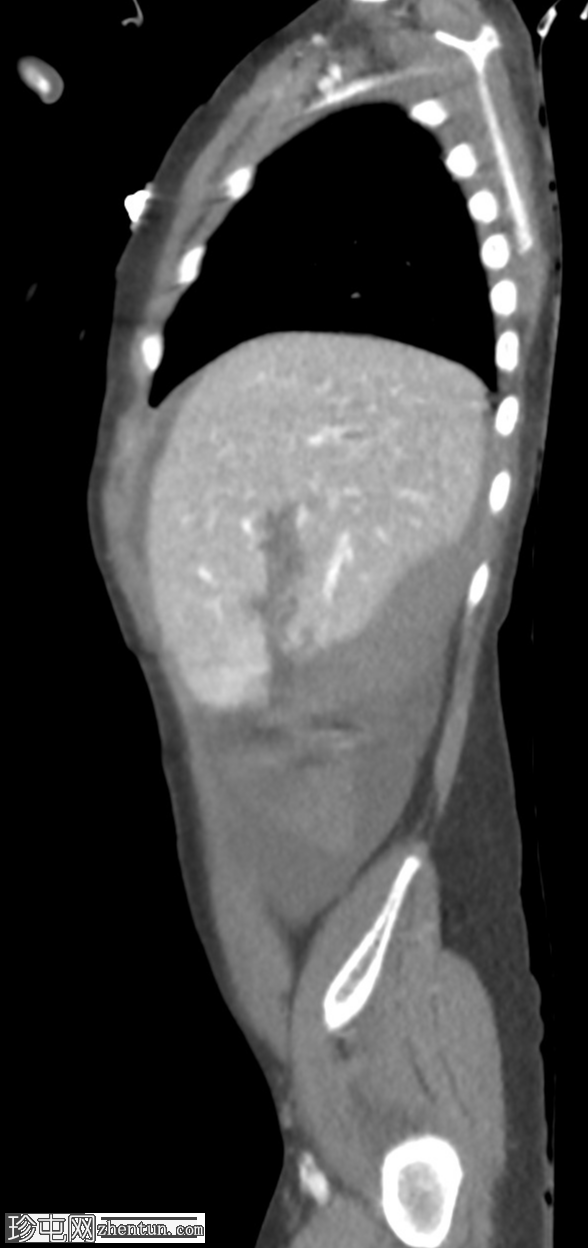

矢状C+门静脉期

AAST IV级肝撕裂伤,伴有大面积不规则肝损伤,累及V段(轴向、冠状、矢状)。

撕裂伤区域内未见活动性造影剂外渗。

可见中等量腹腔积血。

右髂前骨骨折。

无气腹。